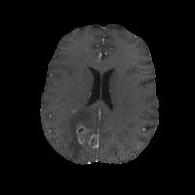

We argue that the sub-optimal paradigm of processing different abstractions within a single CNN pipeline can be remedied through the effective processing of information in a structured manner. Consequently, we devise strategies for disentangling the edge and texture information within a single training pipeline. Figure 2 illustrates how our proposed module, dubbed EG-CNN, can be paired with any existing CNN encoder-decoder to improve segmentation quality near intensity edges. We have applied our EG-CNN to the tasks of brain and liver tumor segmentation in medical images (Figure 3).

(1) Brain MR (2) Liver MR (3) Liver CT (4) Lung CT